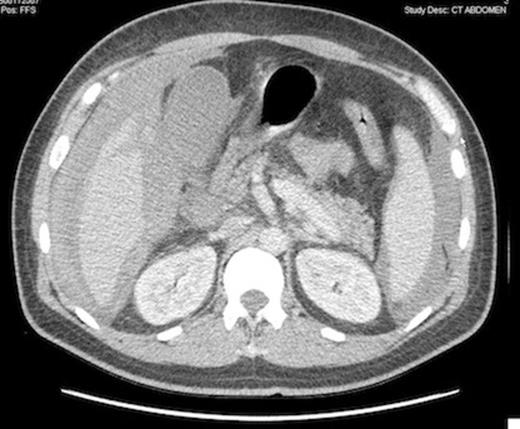

Computed tomography scan demonstrating gallbladder wall thickening and pericholecystic liquid, without gallbladder lithiasis, confirmed by ultrasonography.

One month later the first consolidation chemotherapy (cytarabine + amsacrine) was done and 6 days afterwards the patient presented diarrhoea without abdominal pain or fever. The laboratory investigations revealed a total leukocyte count of 500/mm3, a haemoglobin level of 68 g/L and a platelet count of 11 000/mm3. Despite supportive treatment and antibiotics for a supposed improving colitis, the patient complained of right upper quadrant abdominal pain, high fever (40°C) and hypotension needing ICU admission with the diagnose of abdominal sepsis. A positive Murphy’s sign was observed at physical abdominal examination. The radiological imaging was suggestive for an alithiasic cholecystitis, even though a transverse colon wall thickening was also seen in computed tomography.